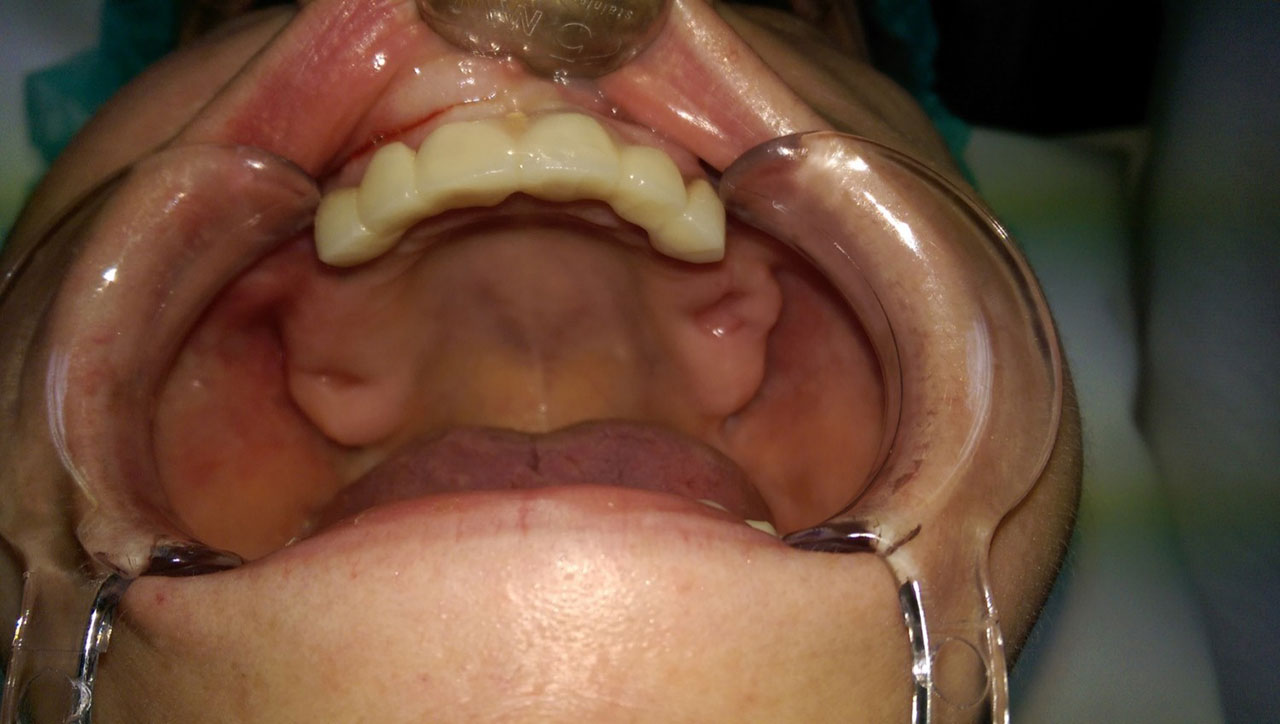

• esettanulmany-08

Műtét másnapján, implantátumok a szájban.

• esettanulmany-09

Így néz ki a hosszútávú ideiglenes híd.(Fém vázzal erősített műanyag híd.)

• esettanulmany-11

Szájban a hosszútávú ideiglenes híd.(Fém vázzal erősített műanyag híd.)